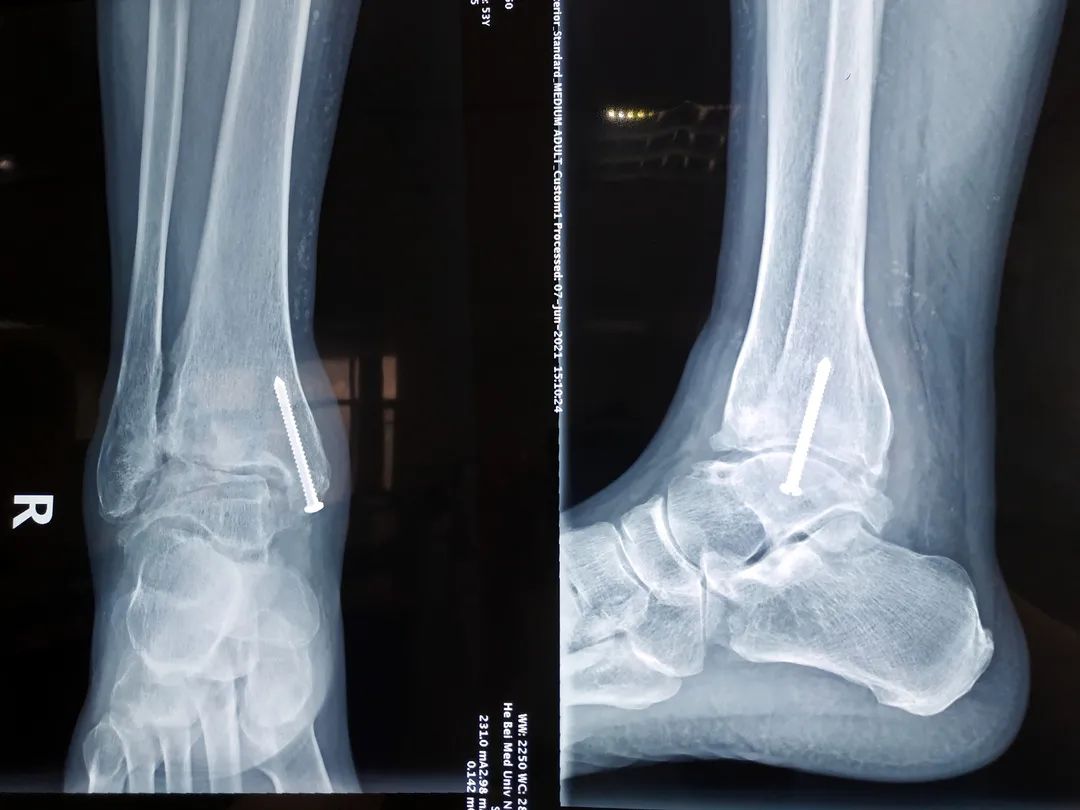

确认了治疗方案后,在张奉琪主任的带领下,治疗团队严格把握手术适应症与禁忌症,顺利完成了省内首例自主InBoneⅡ假体全踝关节置换术。患者术中及术后复查显示踝关节假体力线良好,大小合适,胫距关节假体配合良好。术后14天拆线后即可康复出院。